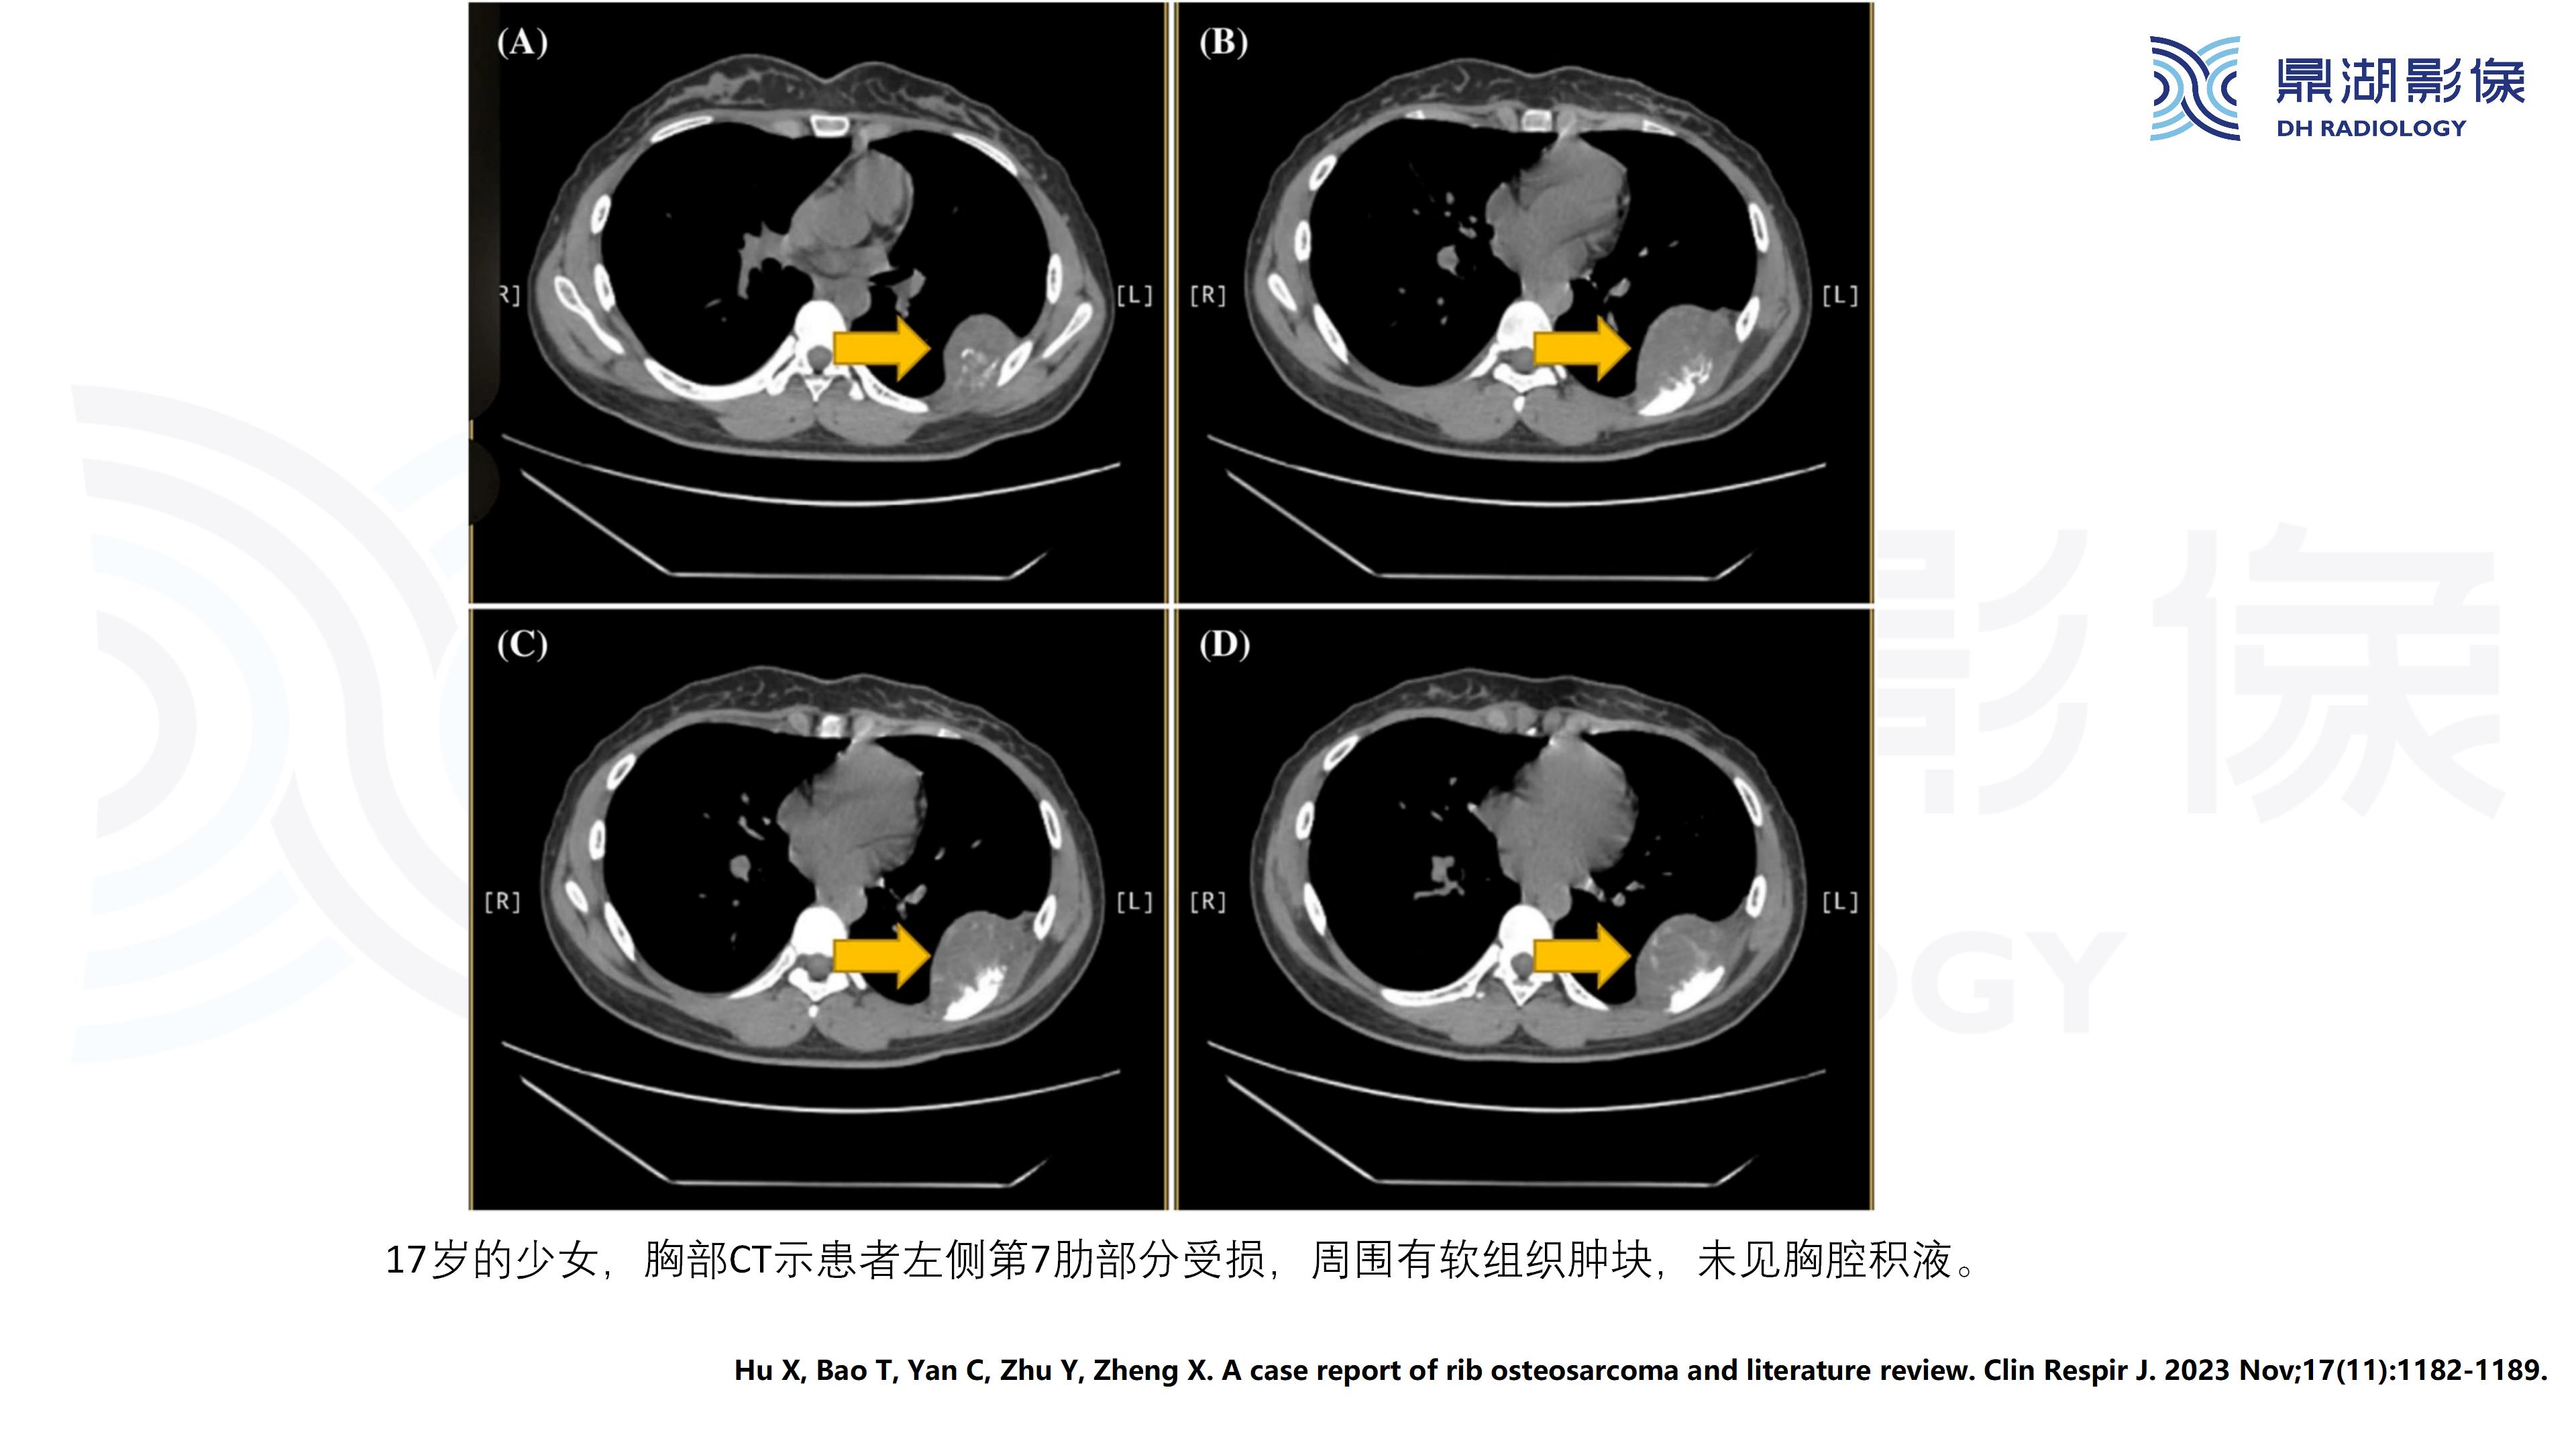

肋骨血管瘤

主诉:发现左侧胸壁局部隆起半年余

现病史:患者女,63岁,半年前活动后出现左侧胸痛,轻度胸闷,无咳嗽咳痰,无头痛头晕,无恶心呕吐,无腹痛等不适。温州大学第一附属医院就诊,未行治疗。半年来左侧胸壁隆起较前明显,活动后轻度胸痛症状,余无明显不适。